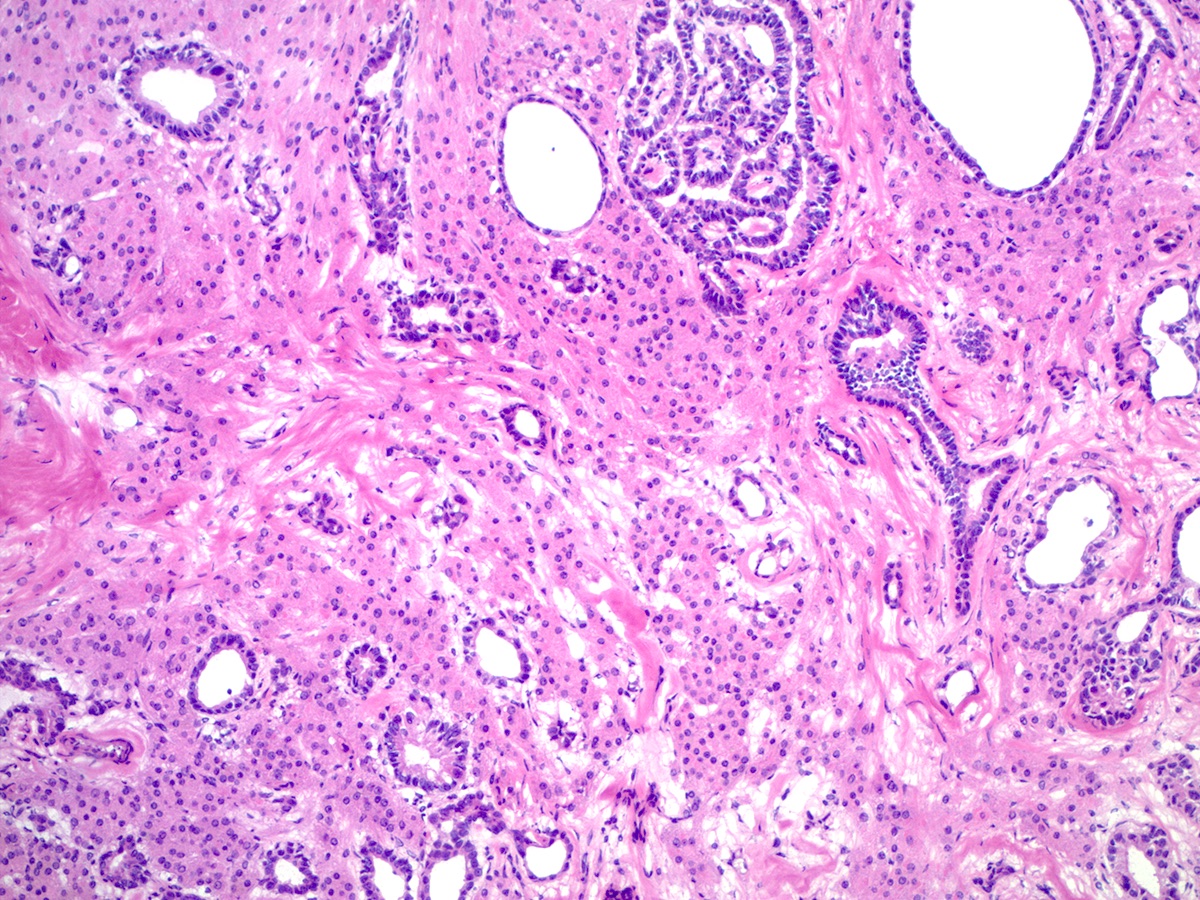

Microscopic (histologic) description

- Well differentiated

- Open or compressed Sertoli cell tubules, admixed with clusters of Leydig cells in the intervening stroma

- Sertoli cells are low columnar to cuboidal with oval to round nuclei, which often show nuclear grooves and small nucleoli

- Leydig cells can be recognized by their round nuclei and abundant eosinophilic cytoplasm with characteristic Reinke crystals and lipofuscin pigment

- No significant atypia or mitotic activity

Microscopic (histologic) images